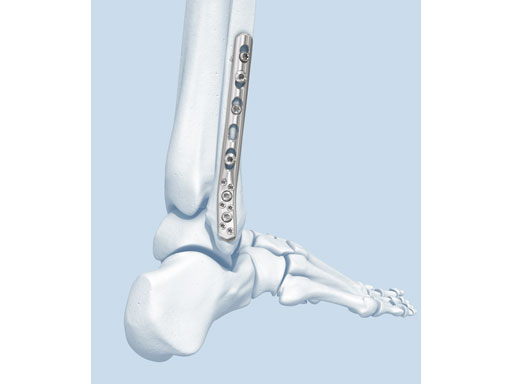

The LCP posterolateral distal fibula plate offers six round locking holes and two coaxial holes distally which accept 2.4 and 2.7 mm locking and cortex screws to provide multiple screw options. The distal holes are slightly divergent to help prevent screw pullout. The coaxial hole accepts both locking and cortex screws and its recess for screw heads minimizes screw-head prominence by allowing the screws to sit more flush with the plate, creating a low-profile construct. Its posterolateral position allows it to be placed deep to the peroneal muscles, minimizing the risk of wound healing problems due to prominence. A 2.7 mm lag screw may be placed through the distal screw cluster, and a syndesmotic screw may also be placed through the plate.

The anatomically precontoured plate shaft is only 2.25 mm thick yet substantially stronger than the one-third tubular plate. The combination holes in the shaft accept 3.5 mm locking screws, 3.5 mm cortex screws, and 4.0 mm cancellous bone screws.

The plate comes in left and right versions and is available in lengths from 77233 mm (3, 4, 5, 6, 7, 9, 11, 13, and 15 holes). It is offered in stainless steel and titanium, sterile, and nonsterile.